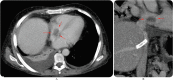

Hypodense thrombus (arrows) seen in the right atrium in the axial (A) and coronal MPR (B) CT images